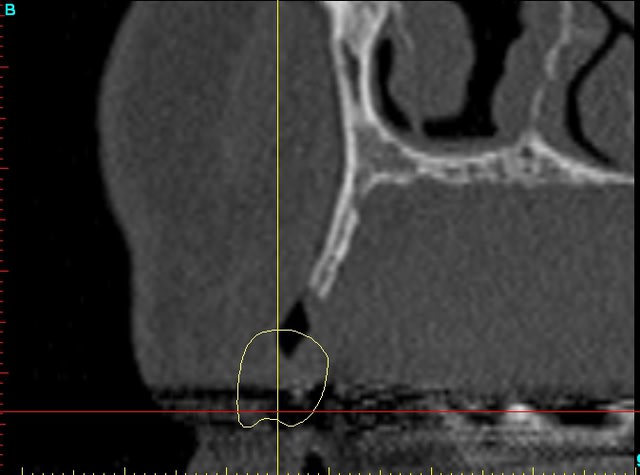

Dar12 dmdcf3 - Eugenol

Dar13 snfr77 - Eugenol

14dar tm9a6n - Eugenol

Dar14 mu6ia0 - Eugenol

15dar srylok - Eugenol

23dar fu8chl - Eugenol

Dar23 cngblb - Eugenol

24dar rfsfid - Eugenol

Dar24 scegbz - Eugenol

25dar yv2tvr - Eugenol

Dar15 gpvqe1 - Eugenol

Dar25 mrwngv - Eugenol

12dar ujxzdu - Eugenol

13dar zaa5vz - Eugenol

22dar mrs1pw - Eugenol

Darcl12.12 - Eugenol